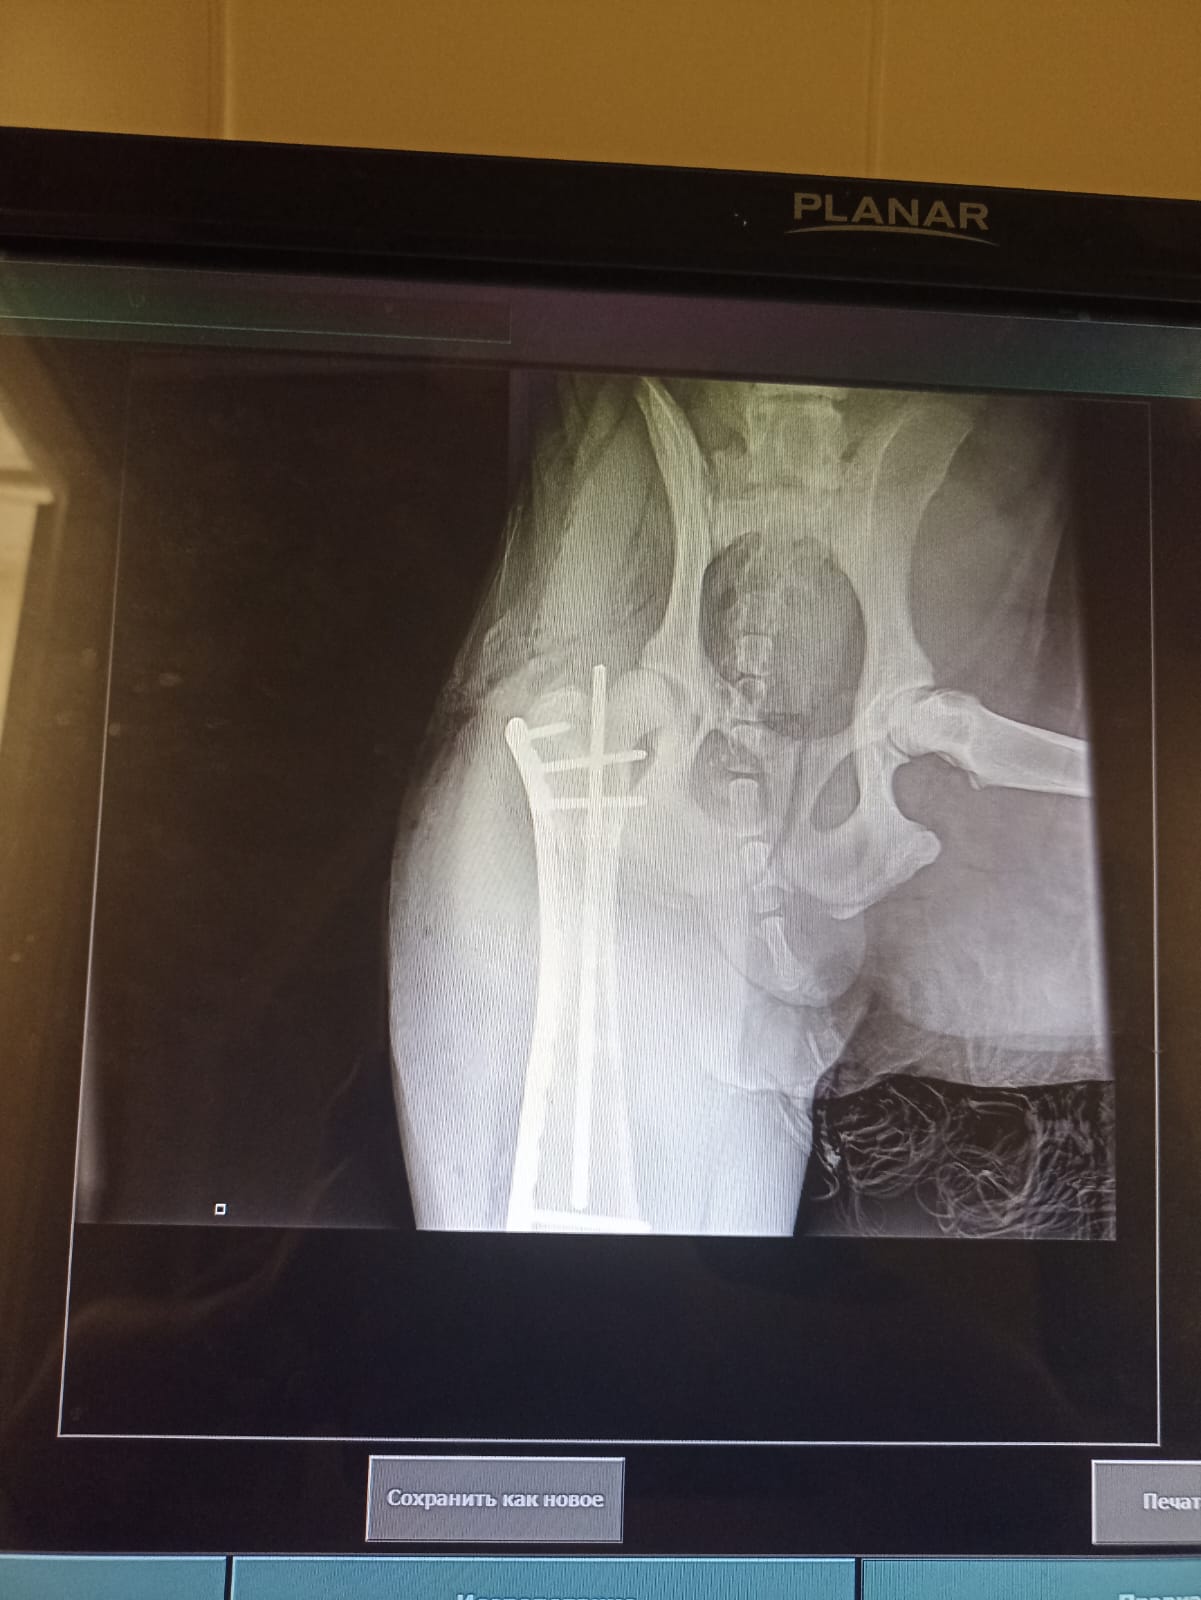

Через 2 недели контрольный рентген и снятие швов.

на 19-е записались на контрольный рентген и снятие швов.